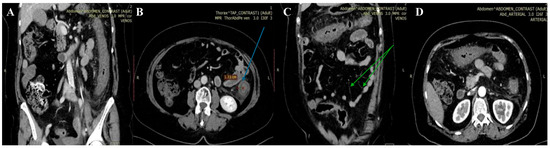

Microbiological investigations ruled out Clostridium difficile, Shigella, Salmonella, and parasitic involvement, and a PCR-based multiplex pathogen GI test detected Shiga-like toxin-producing Escherichia coli (STEC) stx1/stx2 genes. The STEC serotype and subtype could not be determined. The abdominal CT revealed a spastic transverse and descendent large intestine with a thickened circumferential mucosa, suggestive of an inflammatory and infectious process, which progressed over the following days (Figure 1 and Figure 2).

On the third day, the patient underwent a second abdominal CT scan, which showed extensive colonic lesions up to the hepatic flexure and down to the sigmoid and rectum (Figure 2), preserving the mesenteric artery with contrast medium. This picture was compatible with the micro-ischemic lesions found in infectious ischemic colitis [6,7].

Tomographic features very suggestive of bacterial colitis are (1) continuous distribution, (2) an empty colon, (3) the absence of fat stranding, (4) the absence of a “comb” sign, and (5) the absence of enlarged lymph nodes [2]. According to these criteria, our patient had extensive and continuous distribution, collapsed intestines, and the absence of enlarged lymph nodes. However, contrarily, she had pericolic fat stranding and an incomplete “comb” sign, which made the final diagnosis more difficult to determine.

Figure 1. First abdominal CT. Spastic large intestine, with thickened circumferential mucosa (blue arrow), up to 1.33 cm (B), and an incomplete “comb” sign (green arrow) (C). Coronal (A,C) and axial planes (B,D) respectively.

Figure 2. Second abdominal CT. Extensive and continuous lesions, up to hepatic flexure and down to sigmoid with pericolic fat stranding. Coronal (A,C) and axial planes (B,D) respectively.